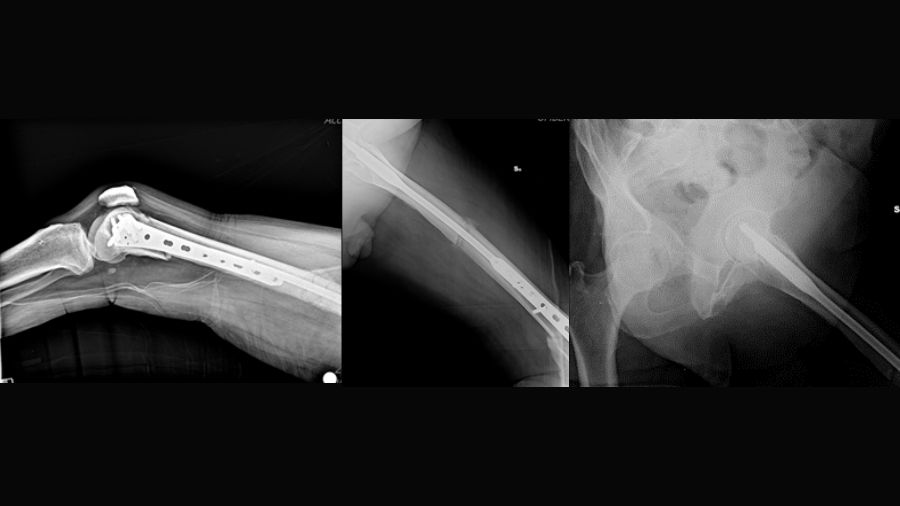

The trifocal femoral fracture (Figure 1) was classified as an obliquely oriented transcervical femoral neck fracture (AO/OTA 31-B2), a displaced shaft fracture (AO/OTA 32-A2), and a supracondylar fracture with intra-articular extension (AO/OTA 33-C2).

This case report describes a high-energy trifocal femoral fracture (intracapsular femoral neck, femoral shaft, and complete distal articular femur) treated with an intramedullary nail, free cannulated screws, and a LISS plate.

Non-contiguous ipsilateral femoral fractures involving the proximal femur, diaphysis, and distal femur are generally associated with high-energy trauma and are poorly described in the literature. Intracapsular femoral neck fractures and complete distal intra-articular fractures (AO/OTA type 33-C) [1] present a more complex clinical picture and are even more rarely documented. Given the rarity and complexity of these injuries, there is no consensus on their optimal surgical management.